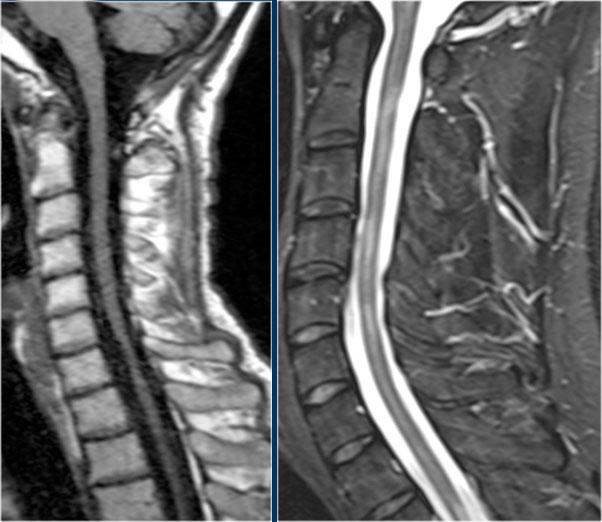

Đây là hình ảnh của bệnh nhân MS lâu năm đang trong đợt cấp.

Có sự ngấm thuốc ở các tổn thương đang hoạt động.

Tiếp tục xem các hình ảnh của cột sống cổ.

Trong tủy sống cũng có nhiều tổn thương.

Trên hình ảnh cắt ngang thấy một tổn thương phía lưng hình tam giác điển hình.

Tiếp tục xem các hình ảnh sau tiêm thuốc tương phản từ.

Ở tủy sống cũng có nhiều tổn thương MS ngấm thuốc.

Viêm Tủy Thị Thần Kinh (Neuromyelitis Optica)

NMO biểu hiện với viêm thần kinh thị giác (mũi tên). Não bình thường. Hình ảnh cung cấp bởi Andrea Rossi

Hình ảnh bên trái của một trẻ em nhập viện với viêm thần kinh thị giác một bên.

Hình ảnh não hoàn toàn bình thường.

Tiếp tục xem MRI cột sống.

Những bệnh nhân có một đợt viêm thần kinh thị giác hoặc viêm tủy và có kết quả xét nghiệm NMO-IgG dương tính có nguy cơ cao tiến triển thành toàn bộ phổ bệnh NMO.

Một tháng sau, trẻ này nhập viện với bệnh tủy cắt ngang cấp tính, tức là các triệu chứng hai bên.

Hình ảnh cho thấy tín hiệu bất thường trong tủy sống kèm phù nề và ngấm thuốc nhẹ.

U tế bào hình sao (astrocytoma) hoàn toàn có thể biểu hiện với hình ảnh tương tự, tuy nhiên dựa vào tiền sử viêm thần kinh thị giác và bệnh tủy cấp tính, chúng ta không nghĩ đến khối u.

Trường hợp này được xác định là NMO và xét nghiệm Ig cho NMO dương tính.